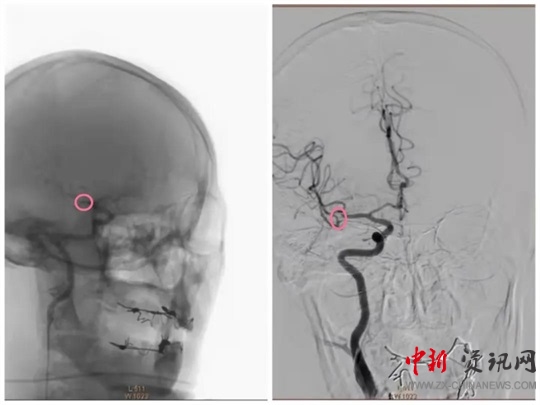

經(jīng)過一系列的術(shù)前準(zhǔn)備并經(jīng)患者家屬同意后,立即繞行病房進(jìn)入介入手術(shù)室,實(shí)施緊急手術(shù)。卒中中心團(tuán)隊(duì)、胸痛中心團(tuán)隊(duì)和介入團(tuán)隊(duì)密切配合,為患者分別實(shí)施了腦動(dòng)脈造影+主動(dòng)脈弓造影+顱內(nèi)動(dòng)脈瘤栓塞術(shù)+冠狀動(dòng)脈造影術(shù)+經(jīng)皮冠狀動(dòng)脈支架植入術(shù),成功把患者從死亡邊緣拉回。目前,患者病情穩(wěn)定,各項(xiàng)指標(biāo)良好。

(動(dòng)脈瘤栓塞前)

(動(dòng)脈瘤栓塞后)